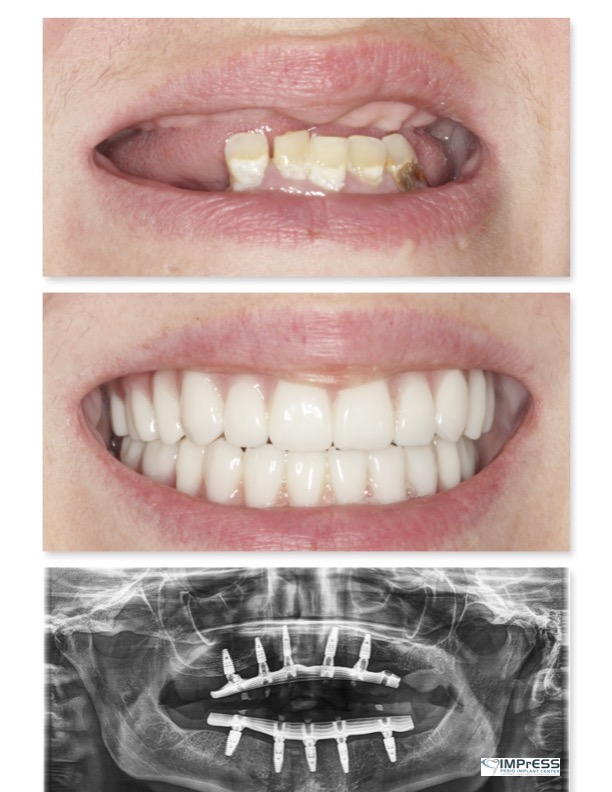

Full Mouth Reconstruction with Fixed Implant Bridge – All on X

All on X implant Full Mouth Implant Reconstruction All on 4 Implants IMPrESS Perio Implant Center Vancouver Burnaby Periodontist Prosthodontist Implant Specialist Dr. Noroozi Periodontist Implant Specialist

mile Makeover with Full Mouth Implants IMPrESS Perio Implant Center Burnaby BC Dr Noroozi

Full Mouth Implant Rehabilitation IMPrESS Perio Implant Center Dr. Noroozi implant Specialist Burnaby Vancouver BC